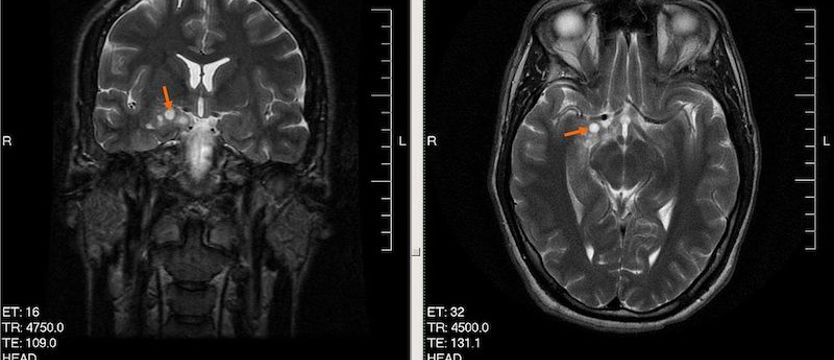

Wysokozróżnicowany glejak u 28-letniego mężczyzny Fot. Wikipedia

Na zdjęciu: Wysokozróżnicowany glejak u 28-letniego mężczyzny

Fot. Wikipedia